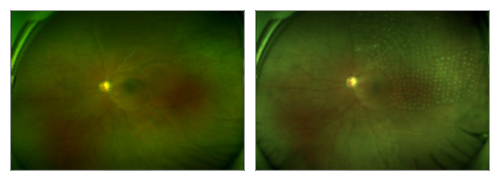

糖尿病患者的眼底照

左图眼底照,该患者已经发生了玻璃体出血,提示需要手术治疗了。右图的眼底照,为患者经过手术治疗后,玻璃体出血完全清除,视力提高,病情缓解。